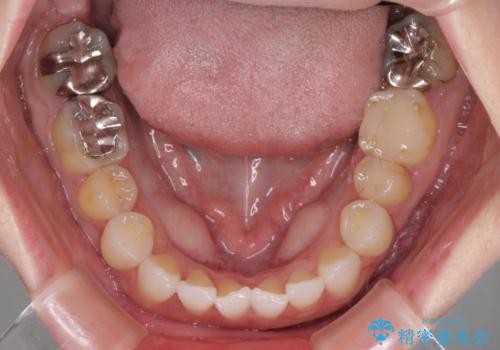

前歯のデコボコをすっきりと インビザライン矯正

- 前歯のデコボコを治したいとのことで来院された患者様です。

下顎が前方位にある方であったため、下顎の歯列全体の後方移動とIPR(歯と歯の間を削る)によってデコボコが解消するように設計し、インビザラインにより治療を行うこととしました。

装着時間が守れず、当初の予定よりも長期間必要となりました。